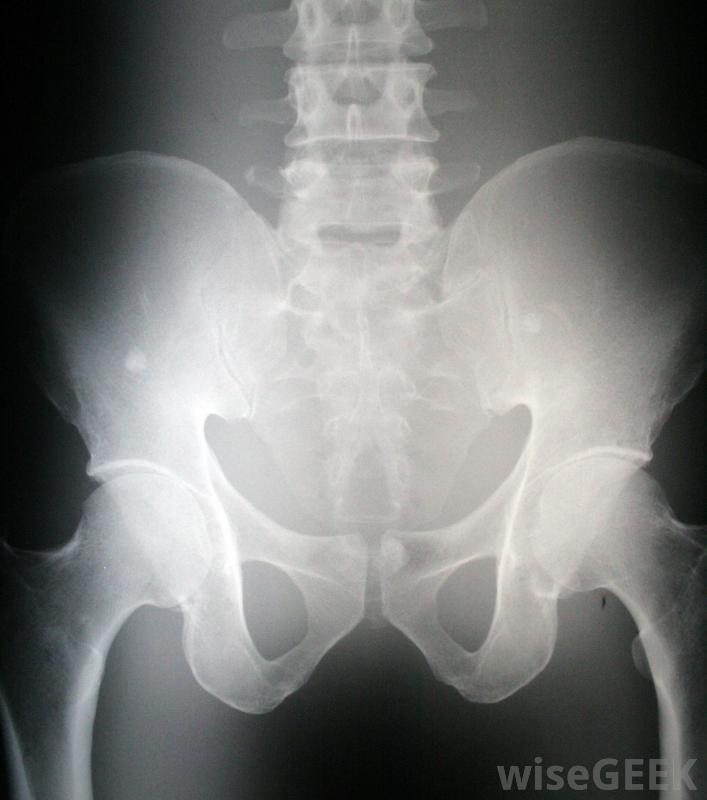

骨盆的X光片,显示骶髂关节SI关节是一种滑膜或活动关节,称为平面关节,这意味着相邻骨骼的相邻表面相当平坦,可以相互滑动,尽管随着年龄的增长,这些表面变得越来越不规则,它们之间只允许少量的运动。有两个SI关节,位于骶骨两侧与髂骨汇合处,骨盆上部两侧的大骨头,形状像蝴蝶的翅膀。它们一起作为一个整体运动,同时吸收大量的重量,这两个因素对SI关节疼痛的诊断具有重要意义